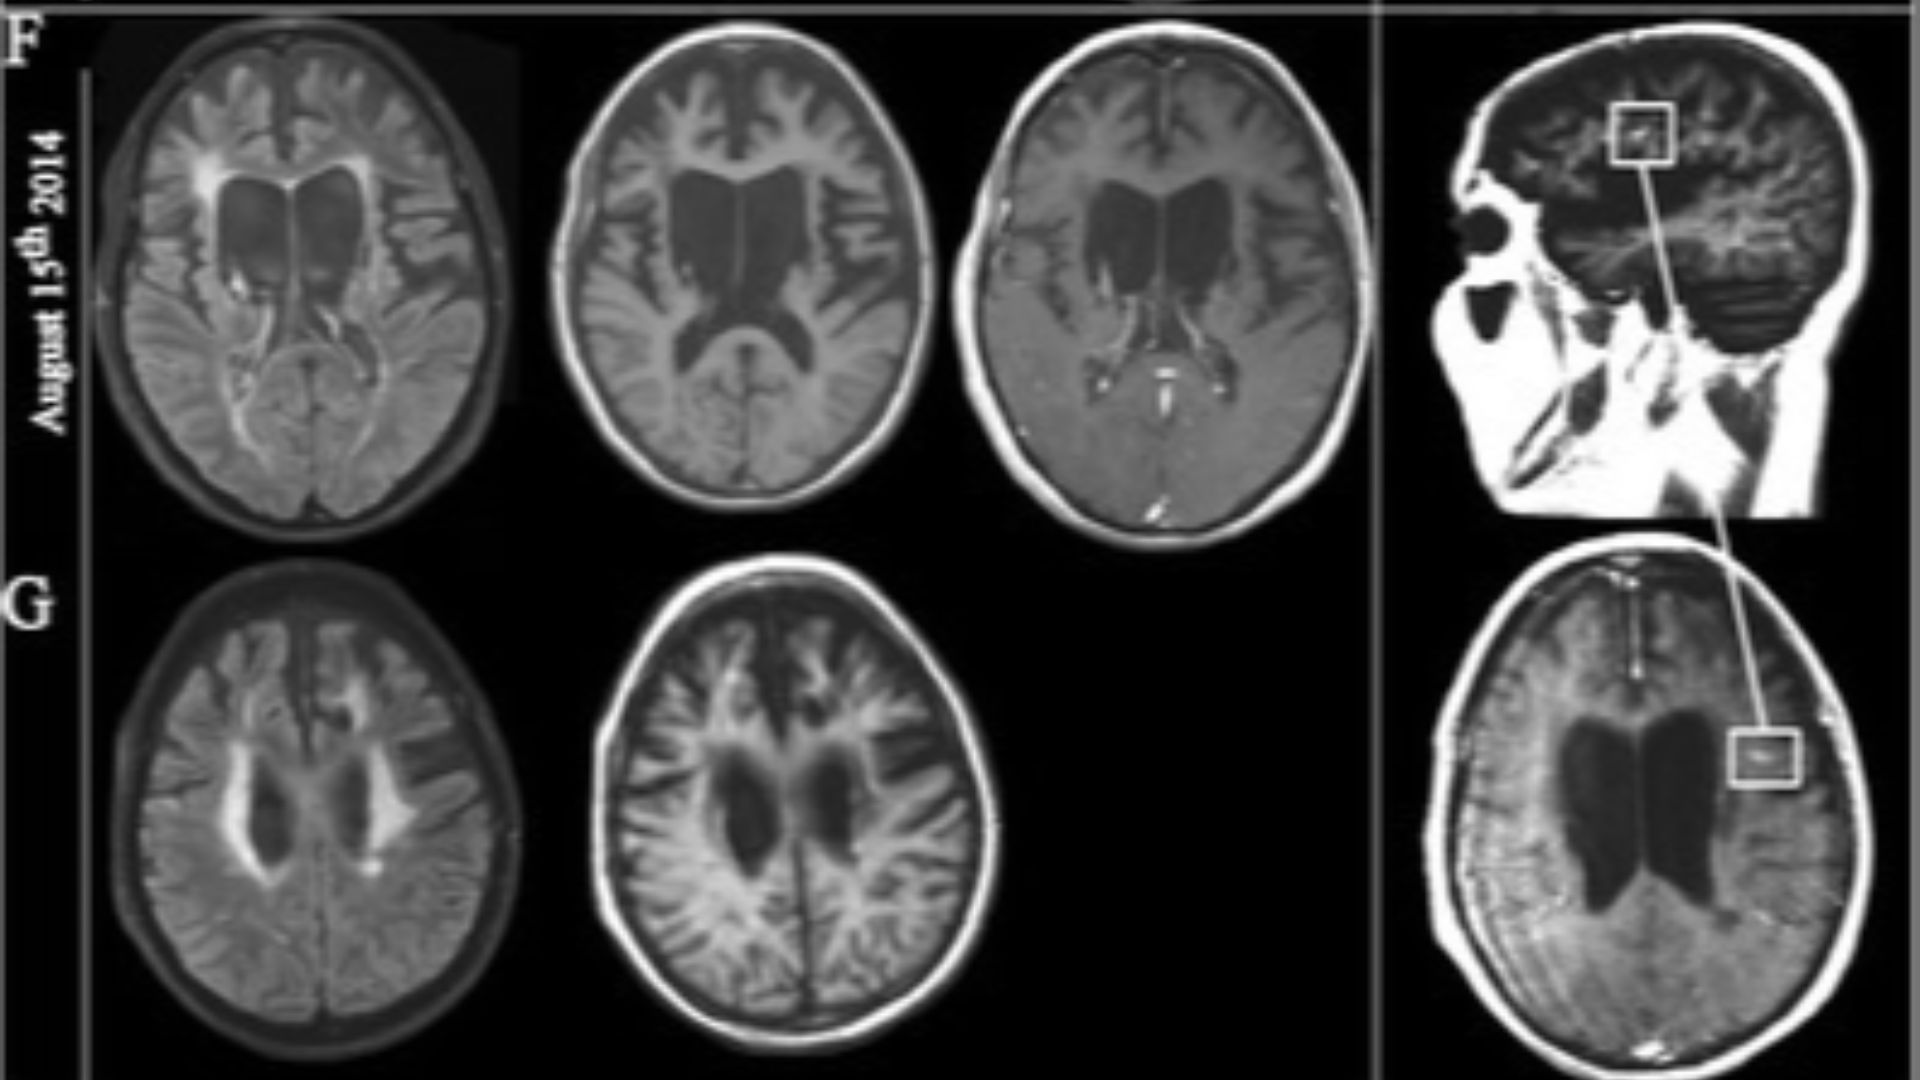

10. Multiple Sclerosis

This disease is linked to the immune system but what causes multiple sclerosis in the first place is still unclear. Multiple sclerosis causes damage to the nerve cells in the brain that negatively affect the spinal chord. It causes mental and physical symptoms like muscle weakness, vision impairment, and loss of coordination.

Yildiz Ö, Pul R, Raab P, Hartmann C, Skripuletz T, Stangel M on Wikimedia